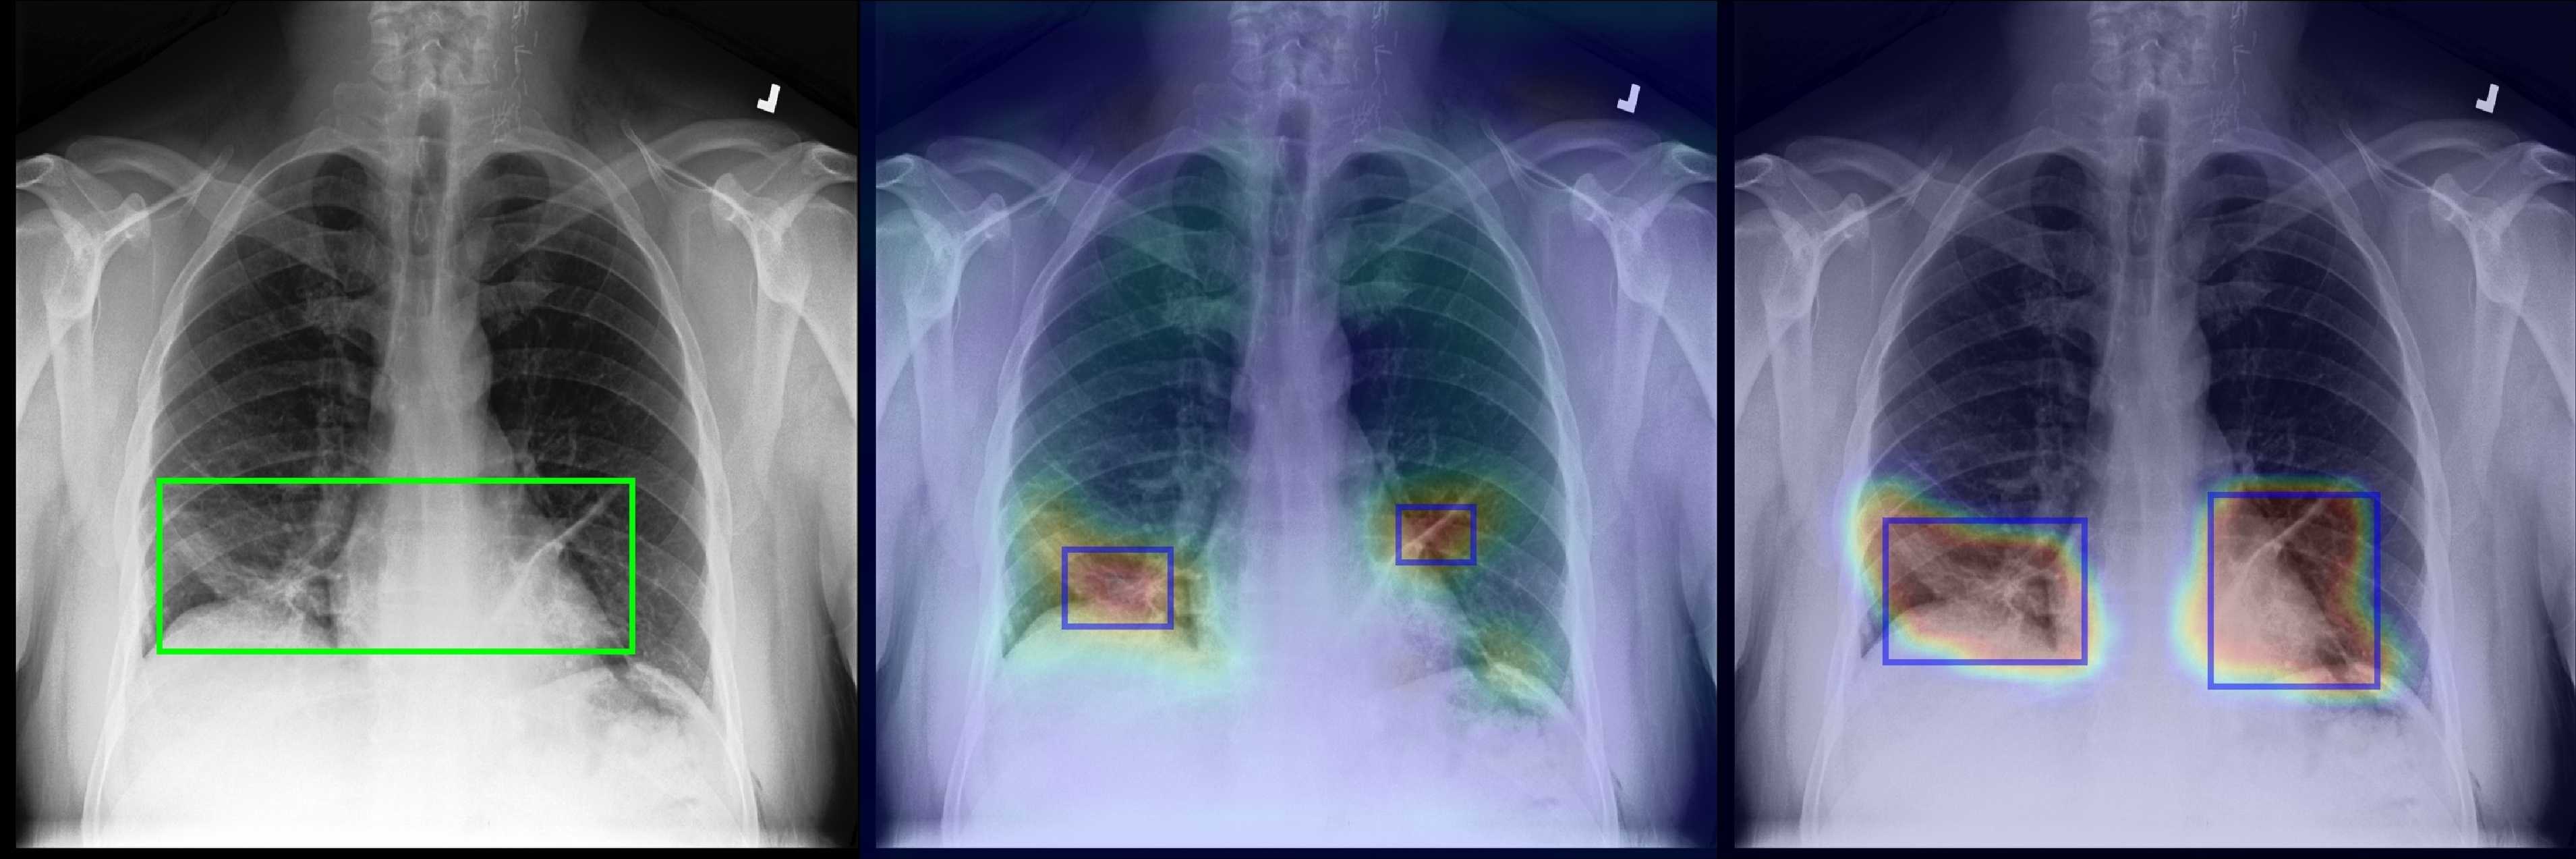

Figure 2 shows a few selected examples of the probability maps generated by PCAM pooling and the class activation maps generated by LSE pooling together with the predicted bounding boxes. Compared to the class activation maps, the probability maps are visually more clear with sharp boundaries around lesion regions. We attribute the improved visual quality to the probabilistic interpretation of the sigmoid-bounded class activation map and explicitly using it for training with global pooling.

We notice the probability maps generated by PCAM pooling tend to enlarge regions of interest in general than class activation maps from LSE pooling, especially when the ground truth regions are small, such as “Nodule” in Figure 2. This may explain the fact that PCAM pooling has relatively larger average false positives than CAM with LSE pooling.

(b) Cardiomegaly

(c) Effusion

Figure 2: Selected samples of localization heatmaps and their bounding boxes generated by LSE pooling and PCAM pooling on the test set of ChestX-ray14 [7]. In each subfigure, the left panel is the original chest X-ray with the ground truth bounding boxes (green), the middle panel is the class activation map and predicted bounding boxes (blue) by LSE pooling, the right panel is the probability map and predicted bounding boxes (blue) by PCAM pooling.